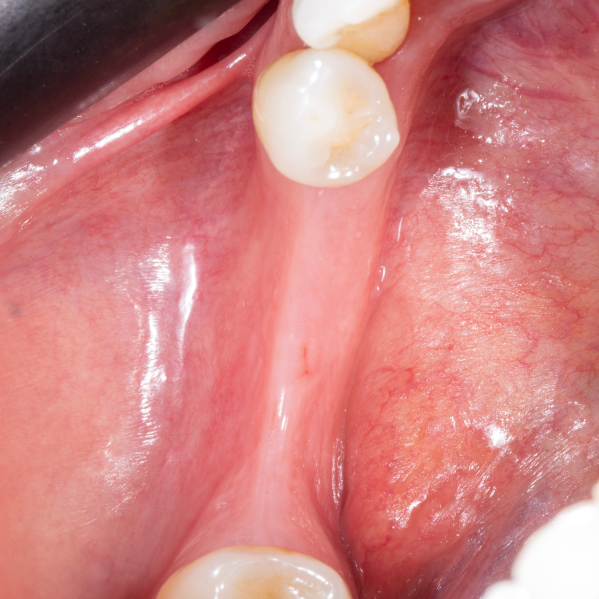

Diş çekiminin yıllar önce yapılmış olmasına bağlı olarak ince kemik varlığında implant ve kemik grefti uygulandı.